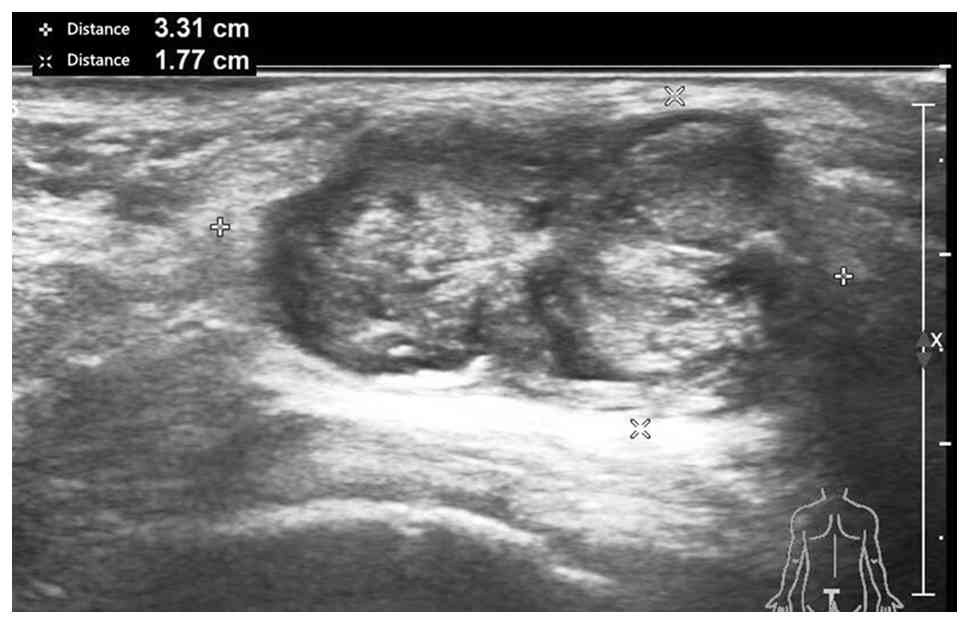

A 79-year old male patient with a 15-day old painless perianal mass was admitted to the First People's Hospital of Xiaoshan (Hangzhou, China) in January 2024. While conducting an anal examination in the lithotomy position, a mass under the epidermis was palpated. The mass was located between the 12 O'clock and 2 O'clock directions, 3.0 cm away from the anal margin. It had a volume of 4.0×3.0×2.0 cm, clear boundaries, soft texture and no notable tenderness or fluctuation sensation. Bilateral superficial inguinal lymph nodes were not enlarged. Digital rectal examination showed no anal fistula or ulcer, and smooth rectal mucosa. Additionally, no other mass was touched, and no blood or purulent discharge was observed on the glove of the examining physician. Colonoscopy of the patient revealed no abnormalities in the colon. A B-ultrasound examination revealed a low heterogeneous echogenic structure (3.31×1.90×1.77 cm) on the left side of the anal canal. The area had distinct boundaries and a regular shape, with no notable blood flow signal (Fig. 1); thus, the mas was considered to be a benign tumor. Detection of tumor serological markers was performed by following the manufacturer's instructions (Abbott Trading (Shanghai) Co., Ltd.) showed that squamous cell carcinoma-associated antigen was 0.92 ng/ml (normal range <1.50 ng/ml), AFP was 0.92 ng/ml (normal range, 0.89–8.78 ng/ml), sugar chain antigen 125 was 5.80 U/ml (normal range, 0–35 U/ml), carbohydrate antigen 199 was 6.70 U/ml (normal range, 0–37 U/ml) and carcinoembryonic antigen was 3.94 ng/ml (normal range, 0–5 ng/ml). The normal ranges of all reagents were provided by Abbott Trading (Shanghai) Co., Ltd. and verified by the Clinical Laboratory Department of the First People's Hospital of Xiaosha, Hangzhou, Zhejiang.

B-ultrasound examination showing a low

heterogeneous echogenic light 3.31×1.90 × 1.77 cm in size and with

a clear boundary detected on the left side of the anal canal.

(Between the two + and between the two × indicates the length and

short diameter of the mass, respectively.)

Figure 1.

B-ultrasound examination showing a low heterogeneous echogenic light 3.31×1.90 × 1.77 cm in size and with a clear boundary detected on the left side of the anal canal. (Between the two + and between the two × indicates the length and short diameter of the mass, respectively.)